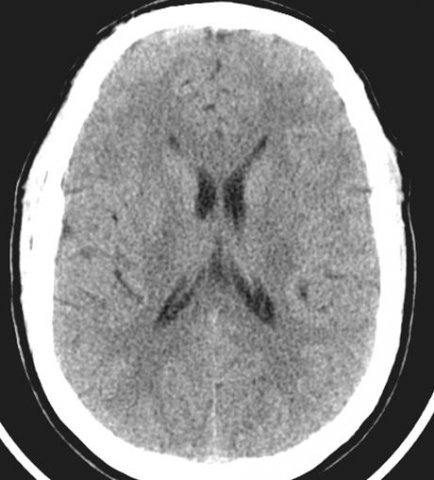

Il s’agit d’un scanner cérébral sans injection à la phase aigue d’un accident ischémique cérébral (AIC) suspecté. L’infarctus peut se traduire par une hypodensité focale ou par un aspect normal comme ici, dans les toutes premières heures.